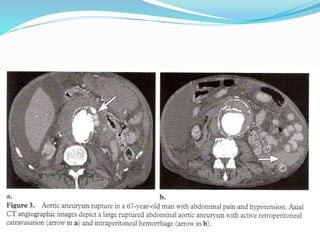

RUPTURE OF ANEURYSM

RUPTURE

 Elective aneurysm repair has a lower mortality rate (9%) than

does emergent repair (22%); therefore, aneurysms are considered

for repair when they are either symptomatic or exceed 5–6 cm in

diameter.

 Imaging findings of A. aneurysm rupture vary from impending

rupture to contained rupture from small aortic leaks with subtle

infiltration of retroperitoneal fat to frank retroperitoneal or intra

peritoneal extra vasation

 UECT

 A retro peritoneal hematoma

 peri aortic blood extension into perirenal spaces

 para renal space or psoas muscle

 Intra peritoneal extension

 CECT

 Active extravasation of contrast noted

 Draped aorta sign

 post wall of aorta is not identifiable or it closely follows the

contour of adjacent vertebral bodies, a consequence of a deficient

aortic wall